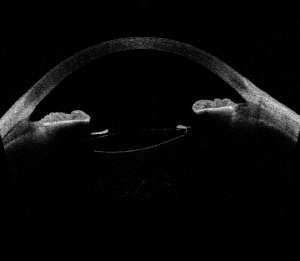

Surgical pearls for IOL explantationPublished: May 17th 2018 | Updated: